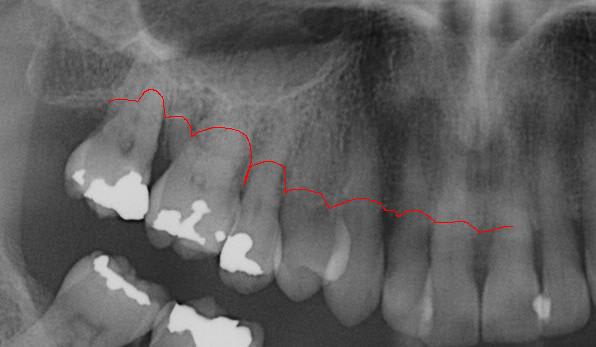

Les panos sont du départ, les photos sont après un nettoyage ...profond et soins.

à l'examen des coupes pano, franchement je ne crois pas que ce soit le bon choix.